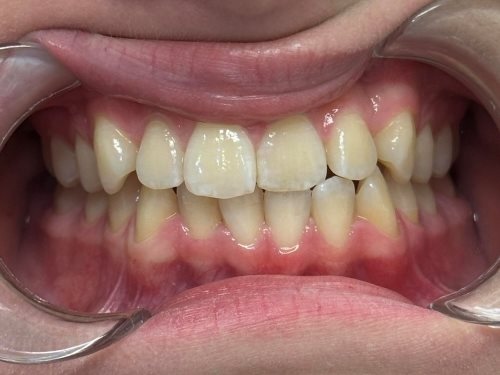

Każdy Pacjent ma inne potrzeby i inną wadę zgryzu, stąd zawsze powinna być przeprowadzana wstępna konsultacja, wyciski/skany, oraz pomiary by jak najlepiej zaplanować cały proces (i czas) leczenia, a przede wszystkim dobrać do potrzeb Pacjenta odpowiedni aparat ortodontyczny.

- wykonania precyzyjnego plan leczenia oraz indywidualnych skanów zębów Pacjenta skanerem wewnątrzustnym,

Aparat Invisalign® w większości przypadków nadaje się dla każdego Pacjenta, który ma zęby wyleczone oraz wyczyszczone z kamienia i osadu.